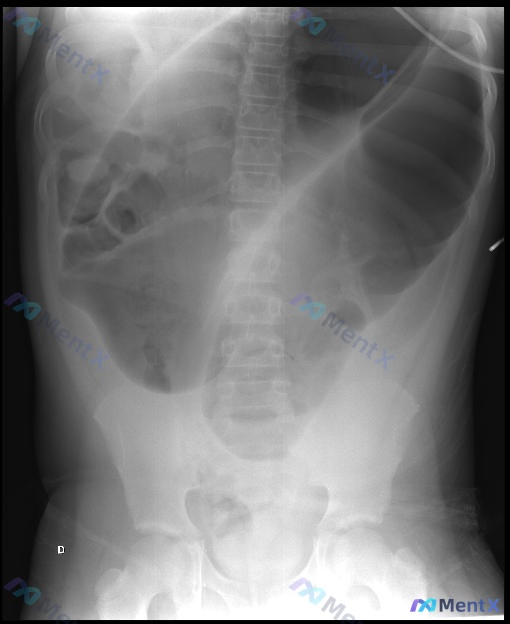

14岁男性腹胀呕吐,X光见巨大U型扩张,下一步怎么选?

影像检查:腹部X光平片已做。

📋答案:最可能的诊断方向为青少年继发性肠套叠(如梅克尔憩室诱发)或特发性乙状结肠扭转;目前最合适的下一步管理措施为内镜检查(配合水溶性造影剂灌肠),兼具诊断与治疗价值。